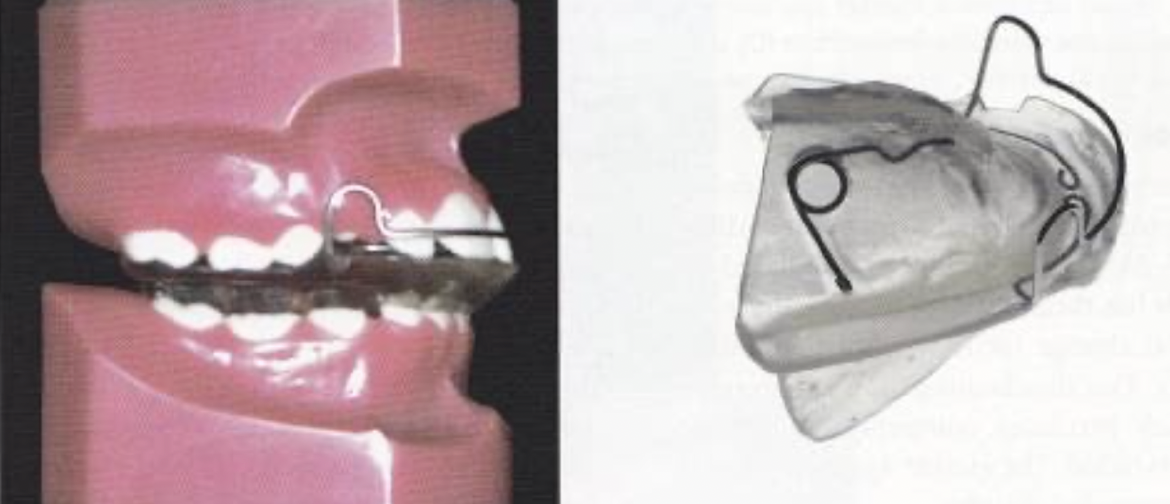

Frankel appliance

唯一Tissue-borne appliance,作用力主要來自軟組織。

- lip pads:隔開 labial m. 讓顎向前,II, III 皆可

- buccal shields: 拉扯骨膜,促進顎骨basal bone 生長

- labial bow & canine loop